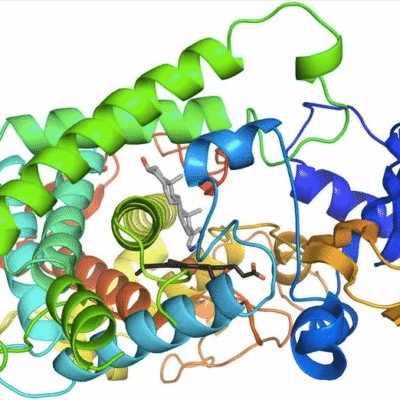

3.3. Theo cơ chế tác động

Kháng sinh ức chế tổng hợp thành tế bào vi khuẩn: beta-lactam, bacitracin, vancomycin Kháng sinh làm xáo trộn chức năng màng tế bào vi khuẩn: colistin, polymyxin.

Kháng sinh ức chế tổng hợp protein: nhóm tetracycline, aminoglycoside tác động lên ribosome 30S của vi khuẩn; nhóm phenicol và macrolide tác động lên tiểu đơn vị 50S của vi khuẩn.

Kháng sinh ức chế quá trình nhân đôi DNA của vi khuẩn: quinolone

Kháng sinh can thiệp vào quá trình tổng hợp acid folic của vi khuẩn: sulfamide.